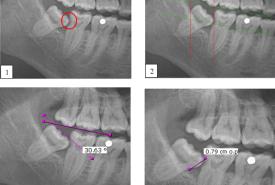

The Incidence of Mandibular Second Molar Distal Caries Associated with Impacted Mandibular Third Molar: A Retrospective Study and Management Guidelines

Original Article 21 Jul, 2025

Farah Hanan Fathihah Jaffar